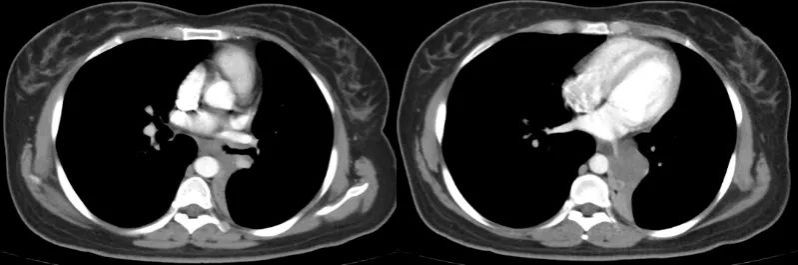

术前胸部CT

胸部CT检查发现,耿女士的左肺支气管内有一个肿物,已经完全堵塞了左肺下叶支气管和部分左肺上叶支气管,雪上加霜的是,肿瘤还完全包绕关键的肺血管——左肺下叶静脉。医生为耿女士进一步完善了气管镜检查,发现在左主支气管开口下2-3cm处可见肿物,肿物沿着管腔延伸至下叶,取活检后病理明确为腺样囊腺癌。

经多学科MDT会诊,强光亮医生建议:“患者目前情况不乐观,根据肿瘤的生长部位,需要全肺切除才能保证肿瘤完整切除。但是肿瘤沿气管外侵很严重,下肺静脉完全被肿瘤包绕,可能侵犯心脏了!总体来说,手术可以尝试,但风险比较大。我们与心脏外科共同制定手术方案,同台手术,保证安全。”

术中,胸外科团队先尝试腔镜下探查。正如术前判断,由于肿瘤播散侵犯了心脏,完全包绕下肺门及关键血管——左肺下叶静脉,前后肺门都难以游离出下肺静脉。强光亮冷静思索后决定:可以从心包内尝试。强光亮在安全距离打开心包,探查到关键血管——上下肺静脉。然而,手术团队又面临新的问题:心包内下肺静脉也被肿瘤包绕,难以游离出足够的长度。

肿瘤严重包绕下肺静脉